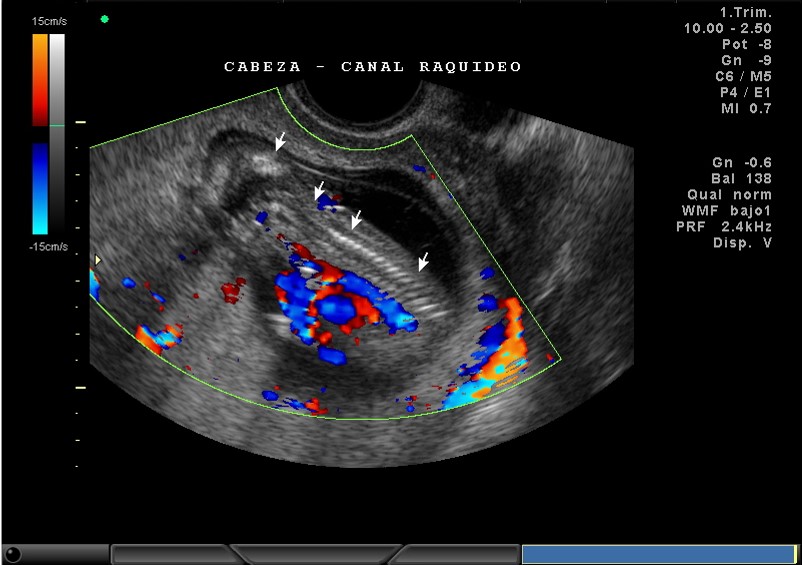

2D Y COLOR, NUCA, CANAL RAQUIDEO, CORAZON Y VASOS